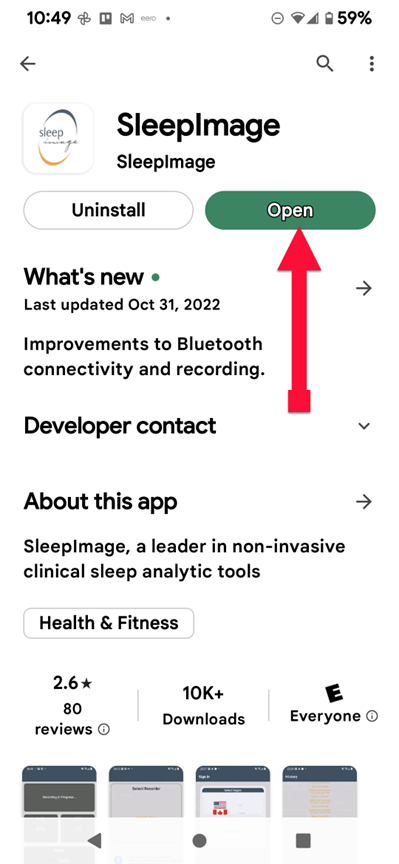

SLEEPIMAGE APP (Android)

SLEEPIMAGE APP (Android)

SLEEPIMAGE APP (Android)

SLEEPIMAGE APP (Android)

SLEEPIMAGE APP (Android)

SLEEPIMAGE APP (Android)

SLEEPIMAGE APP (Android)

SLEEPIMAGE APP (Android)

SLEEPIMAGE APP (Android)

SLEEPIMAGE APP (Android)

SLEEPIMAGE APP (Android)

SLEEPIMAGE APP (Android)

SLEEPIMAGE APP (Android)

SLEEPIMAGE APP (Android)

SLEEPIMAGE APP (Android)

SLEEPIMAGE APP (Android)

SLEEPIMAGE APP (Android)

SLEEPIMAGE APP (Android)

SLEEPIMAGE APP (Android)

SLEEPIMAGE APP (Android)

SLEEPIMAGE APP (iPhone)

SLEEPIMAGE APP (Android)

SLEEPIMAGE APP (Android)

SLEEPIMAGE APP (Android)

SLEEPIMAGE APP (Android)

SLEEPIMAGE APP (Android)

SLEEPIMAGE APP (Android)

SLEEPIMAGE APP (Android)

SLEEPIMAGE APP (Android)